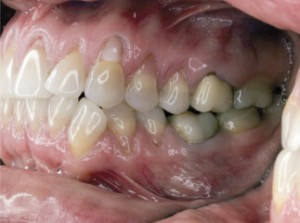

| Pacjentka w wieku 40 lat przed leczeniem. Mnogie (wysokie i szerokie) recesje dziąsła, ryc. 3 | ||